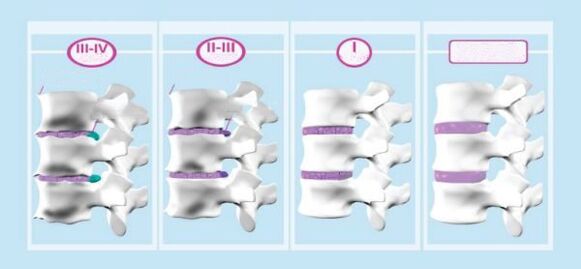

Ang cervical osteochondrosis, tulad ng osteochondrosis ng iba pang mga gulugod, ay bubuo sa mga yugto. Mayroong 3 yugto ng pag -unlad ng sakit.

1 degree

Ito ay nailalarawan sa simula ng pagkawasak ng mga intervertebral disc.

Ang mga bitak ay bumubuo sa fibrous singsing, ang lakas at pagkalastiko ng disk ay nabuo, bumababa ang taas nito, dahil sa kung saan ang mga ugat ng nerbiyos ay pinisil.

Lilitaw ang isang katangian ng sakit na sakit. Minsan sa 1 yugto (preclinical) ang nasabing sakit ay maaaring wala, at ang osteochondrosis ay nagpapatuloy na may katamtamang kakulangan sa ginhawa sa leeg.

2 degree

Kung ang osteochondrosis ng 1st degree ay hindi ginagamot o ang paggamot ay hindi epektibo, kung gayon ang isang talamak na kondisyon ay nangyayari, na kung saan ay ang ika -2 antas ng osteochondrosis.

Ang sakit ay nagiging pare -pareho, ang pagkawasak at selyo ng intervertebral disc ay nagpapatuloy at humahantong sa maliit na dislocations ng cervical vertebrae.

Sa cervical osteochondrosis, ang isang bumabagsak na sindrom ng ulo ay maaaring umunlad sa yugtong ito. Ang sindrom na ito ay nailalarawan sa pamamagitan ng matinding sakit, at ang isang tao ay pinipilit na suportahan ang kanyang ulo sa isang nakapirming estado upang mabawasan ang sakit.

3 degree

Ang cervical osteochondrosis ng ika -3 degree ay sinamahan ng mga sumusunod na palatandaan:

- sakit ng ulo;

- pagduduwal;

- pagkahilo;

- cervical "bastards";

- Paglabag sa pagiging sensitibo ng itaas na mga paa't kamay.

Ang fibrous singsing ay halos nawasak, na humahantong sa mga komplikasyon ng osteochondrosis - protrusion ng intervertebral disc o intervertebral hernia.

Sa 3 yugto ng osteochondrosis, ang intensity ng sakit ay maaaring bumaba, dahil ang apektadong cartilaginous tissue sa intervertebral disk ay hindi umiiral, na nangangahulugang walang mapagkukunan ng sakit, ngunit ang pinching ng mga ugat ng nerbiyos ay nananatili, kaya ang sakit ay hindi ganap na umalis.